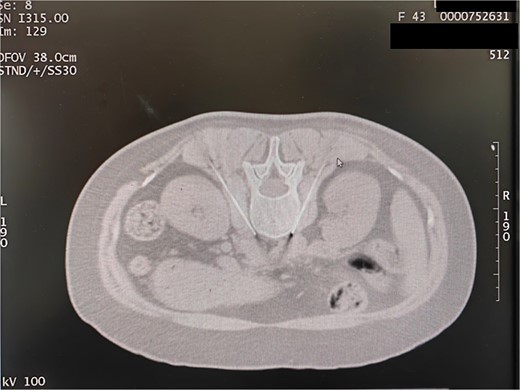

Following the withdrawal of the needle and a subsequent CT scan, no pneumothorax was observed in the lung window, leading to the conclusion of the treatment. Subsequently, RFN of the thoracic sympathetic was performed. Under CT guidance, L3 sympathetic ganglion RFN was initiated. The patient assumed a prone position in the CT room with a soft pillow under the abdomen, and vital signs, such as blood pressure and heart rate, were monitored. The L2–3 vertebral body was identified through CT localization, and after a plain scan, the optimal puncture level and skin puncture point were selected. The proposed depth of needle penetration at the puncture point, as well as its angle and distance from the midline, were measured using a CT tool ruler. The angle and relative distance between the CT bed and the rack displayed at that level were also recorded (Fig. 6).